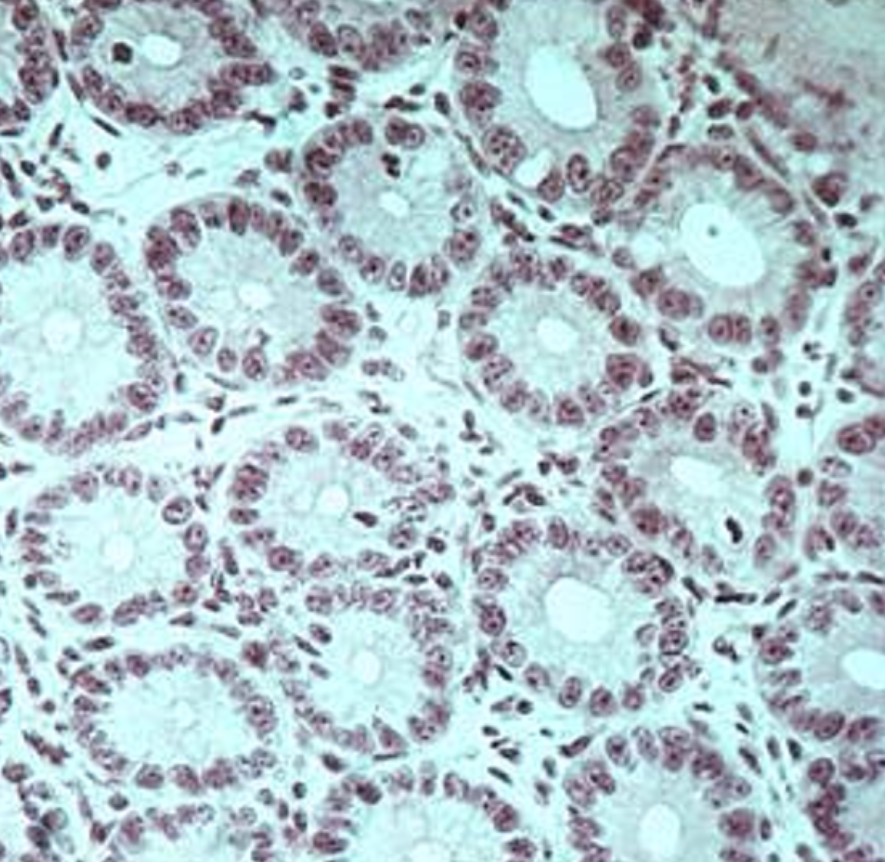

the arrows point to

goblet cells

villi

this is from the

ileum